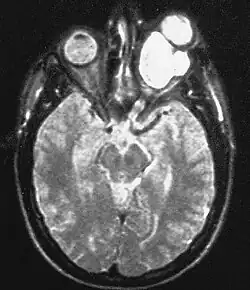

| Magnetic resonance image of a large retrobulbar optic nerve tumor causing massive proptosis | |

Optic nerve gliomas are diagnosed using magnetic resonance imaging (MRI) and CT scans.[5] The tumor adopts a fusiform appearance, appearing wider in the middle and tapered at the ends.[5] Enlargement of the optic nerve along with a downward kink in the mid-orbit is usually observed.[5] While CT scans allow for optic nerve evaluation, MRI allows for intracranial evaluation to observe if the tumor has extended to other regions such as the optic chiasm and hypothalamus.[6]